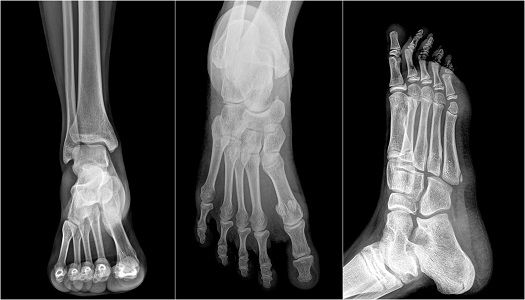

Snowboarders fracture. A prospective study for 3 seasons from 1998 to 01. A type 1 fracture is an articular process chip fracture of the talus with no extension into the talofibular joint. Comminuted fracture through the lateral talar process.

It accounts for less than 1% of reported ankle injuries. “Snowboarder’s fracture” is a colloquialism commonly used to describe a fracture of the lateral process of the talus. Fracture of the lateral process of the talus is an injury unique to snowboarders and is of particular clinical relevance because it masquerades as an anterolateral ankle sprain and is difficult to detect on standard radiographic views.

Snowboarding spinal injury patterns have not been described. This particular injury results in persistent lateral pain in the affected ankle yet is difficult to spot in a plain X-ray image. Fractures of the lateral process of the talus (LPT) are considered rare, accounting for less than 1% of all ankle injuries in the general population.

The talus is the lower bone that makes up the ankle joint and the top bone that makes up the subtalar joint. This injury typically presents with anterolateral ankle pain, and the typical mechanism is dorsiflexion, inversion of the hindfoot, axial loading, and internal rotation (5,7,30). Many of these fractures are not visible on plain radiographs and require computed tomography imaging to be diagnosed.

Snowboarder’s fracture is a rare ankle fracture that is on the rise. The talus is an important bone as it creates multiple joints in the foot/ankle;. Fractures of the lateral process of the talus (Figure 4), also known as the “snowboarder’s fracture”, typically occur when a snowboarder is landing after a jump or fall, with the ankle in forced dorsiflexion and inversion.